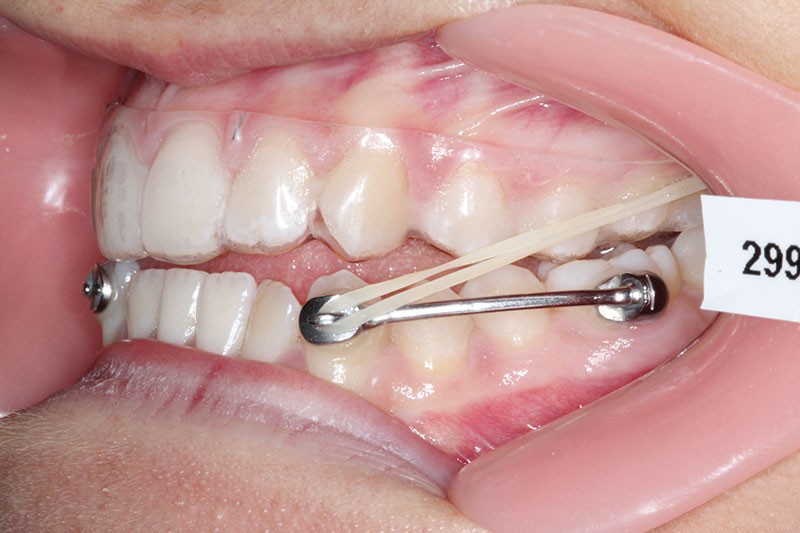

1re phase : recul des secteurs latéraux mandibulaires avec le Motion Classe III Carriere (fig. 4 à 6)

Nous mettons en place des bras latéraux Motion associés à des élastiques intermaxillaires ancrés sur des brackets sur 17 et 27 et une gouttière thermoformée maxillaire portée jour et nuit :

• 1er mois : élastiques 6 oz. 1/4”

• 2e mois et suivants : élastiques 6 oz.1/4“

L’objectif de cette étape est d’obtenir un recul des secteurs latéraux mandibulaires afin de positionner les molaires et canines en classe I et de réorienter le plan d’occlusion en haut en avant.